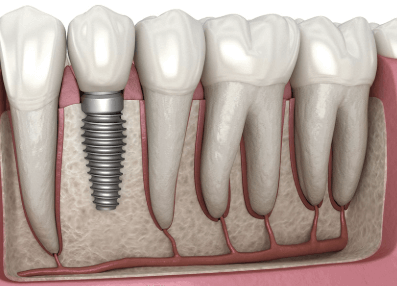

정기적인 검진 필요성

임플란트가 자리 잡은 후에도 6개월~1년에 한 번씩 정기 검진을 받아야 합니다. 임플란트 주위염을 예방하려면 치과에서 전문적인 스케일링과 유지 관리를 받아야 합니다. 임플란트 시술 후 관리가 제대로 이루어지지 않으면 실패 확률이 높아질 수 있으므로 주의사항을 철저히 지키는 것이 중요합니다.